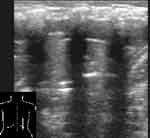

При снижении воздушности легочной ткани вследствие пневмонической инфильтрации или ателектаза, она становится эхографически видимой, имеет пониженную эхогенность и однородную эхоструктуру. Контур пневмонического очага в начале заболевания довольно ровный, форма может быть различной. В случае долевой пневмонии он повторяет форму доли, при сегментарной может иметь пирамидальную форму с основанием, обращенным к плевре, очаговой — неправильную, близкую к округлой. В безвоздушных пневмонических очагах бывают видны эхогенные, ветвящиеся, прерывистые полоски, являющиеся заполненными воздухом бронхами, а так же трубчатые анэхогенные структуры — сосуды или заполненные жидкостью бронхи и реже — тонкие линейные эхогенные полоски — соединительно-тканные межсегментарные перегородки (Рис. 2, 3). Эхогенная полоска плевры над безвоздушным участком (пневмоническим очагом или ателектазом) выглядит гораздо тоньше, чем над воздушным легким. Но это происходит не из-за «истончения плевры» [1], а из-за отсутствия составляющей отражения от поверхности воздушного легкого в комплексе плевральной эхогенной полоски. Пневмонические участки в наших наблюдениях имели несколько пониженную или среднюю эхогенность и не были гиперэхогенными, как указывают некоторые авторы [9, 2]. По мере же пневматизации при рассасывании инфильтрата в них появлялись множественные сливающиеся гиперэхогенные участки пневматизации. А высокая эхогенность при «свежих» пневмониях отмечалась за безвоздушными участками на границе с воздушной легочной тканью вследствие дистального усиления.

[Увеличить]

Рис. 2. Пневмонический очаг, содержащий эхогенные полоски воздуха в бронхах и тонкую межсегментарную перегородку.